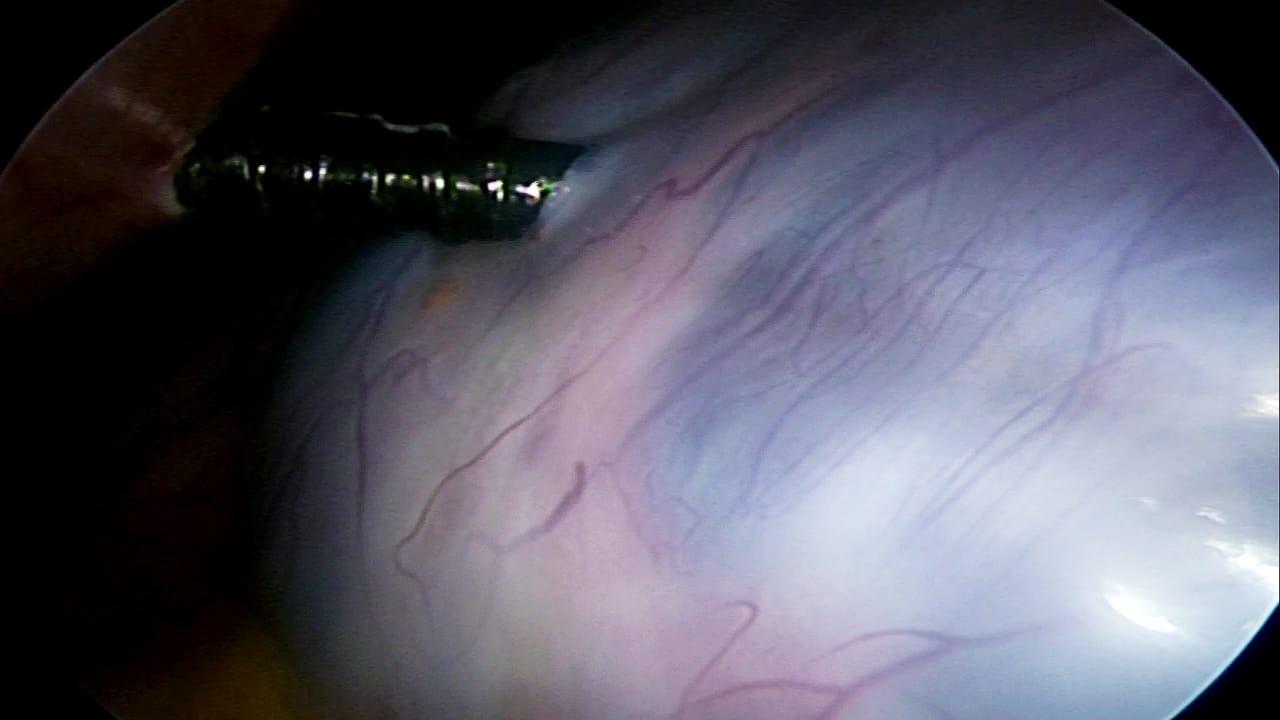

Advanced laparoscopic techniques for gynecological conditions.

Innovative laparoscopic methods for preserving fertility.

Laparoscopic myomectomy for uterine fibroids.

Laparoscopic solutions for pelvic organ prolapse.

Safe and effective laparoscopic tubal ligation procedures.

Laparoscopic tuboplasty for restoring fertility.

Laparoscopic techniques for ovarian tumor removal.

Complete laparoscopic hysterectomy for various conditions.